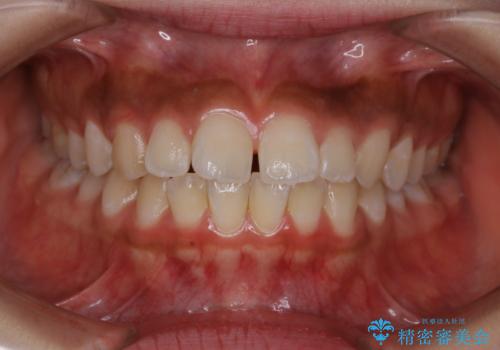

短期間ですきっ歯を改善:インビザラインLite

- 上の歯がすきっ歯なのと、歯が出ている気がするとご相談にいらした方です。

奥歯の噛み合わせに大きな問題がなく、患者様のご希望もあったため、前歯部メインで治療するインビザラインLiteで治療を行いました。

横顔のシルエットが改善し、口元もスッキリとなりました。